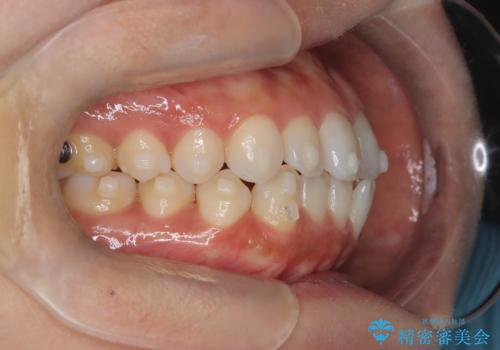

前歯の叢生を非抜歯で改善|インビザライン+IPR・遠心移動・FIX保定

- 前歯部のガタガタ(叢生)を非抜歯で改善するため、インビザラインによるマウスピース矯正を計画しました。抜歯は行わず、歯間をわずかに削るIPR(ディスキング)と奥歯を後方に移動させる遠心移動を併用して、歯を並べるスペースを確保します。歯列が整った後は、FIXリテーナー(固定式保定装置)で後戻りを防止し、安定した歯並びを維持します。

歯を抜きたくないというご希望に応え、インビザラインを用いて非抜歯で歯列を整えました。前歯に必要なスペースを確保するため、歯間をわずかに削るIPRと奥歯を後方に移動する遠心移動を組み合わせました。これにより自然で美しい歯並びを実現。治療終了後は、歯の裏側に目立たないFIXリテーナーを装着し、歯列の後戻りを効果的に防ぎました。患者様は治療中も審美的にストレスなく過ごされ、満足度の高い結果を得られました。